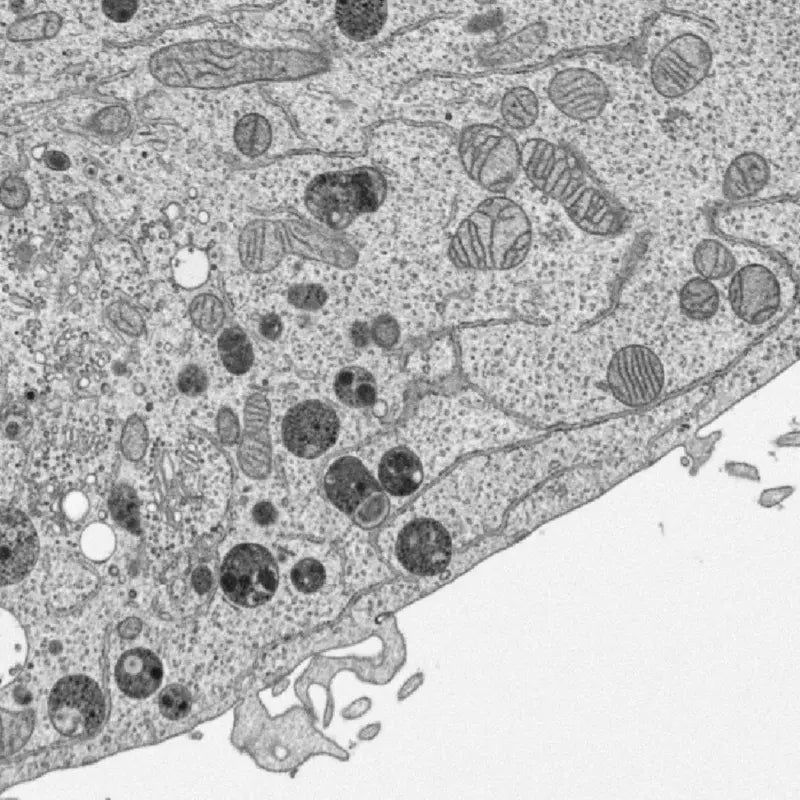

Mitochondrial function

The mitochondria, often called the powerhouses of the cell, operate similarly in both species. These structures help generate cellular energy. Many compounds that support normal mitochondrial activity have comparable safety considerations across cats and dogs when used within normal ranges.

Image Credit: Louisa Howard, Dartmouth Electron Microscope Facility. Public Domain.